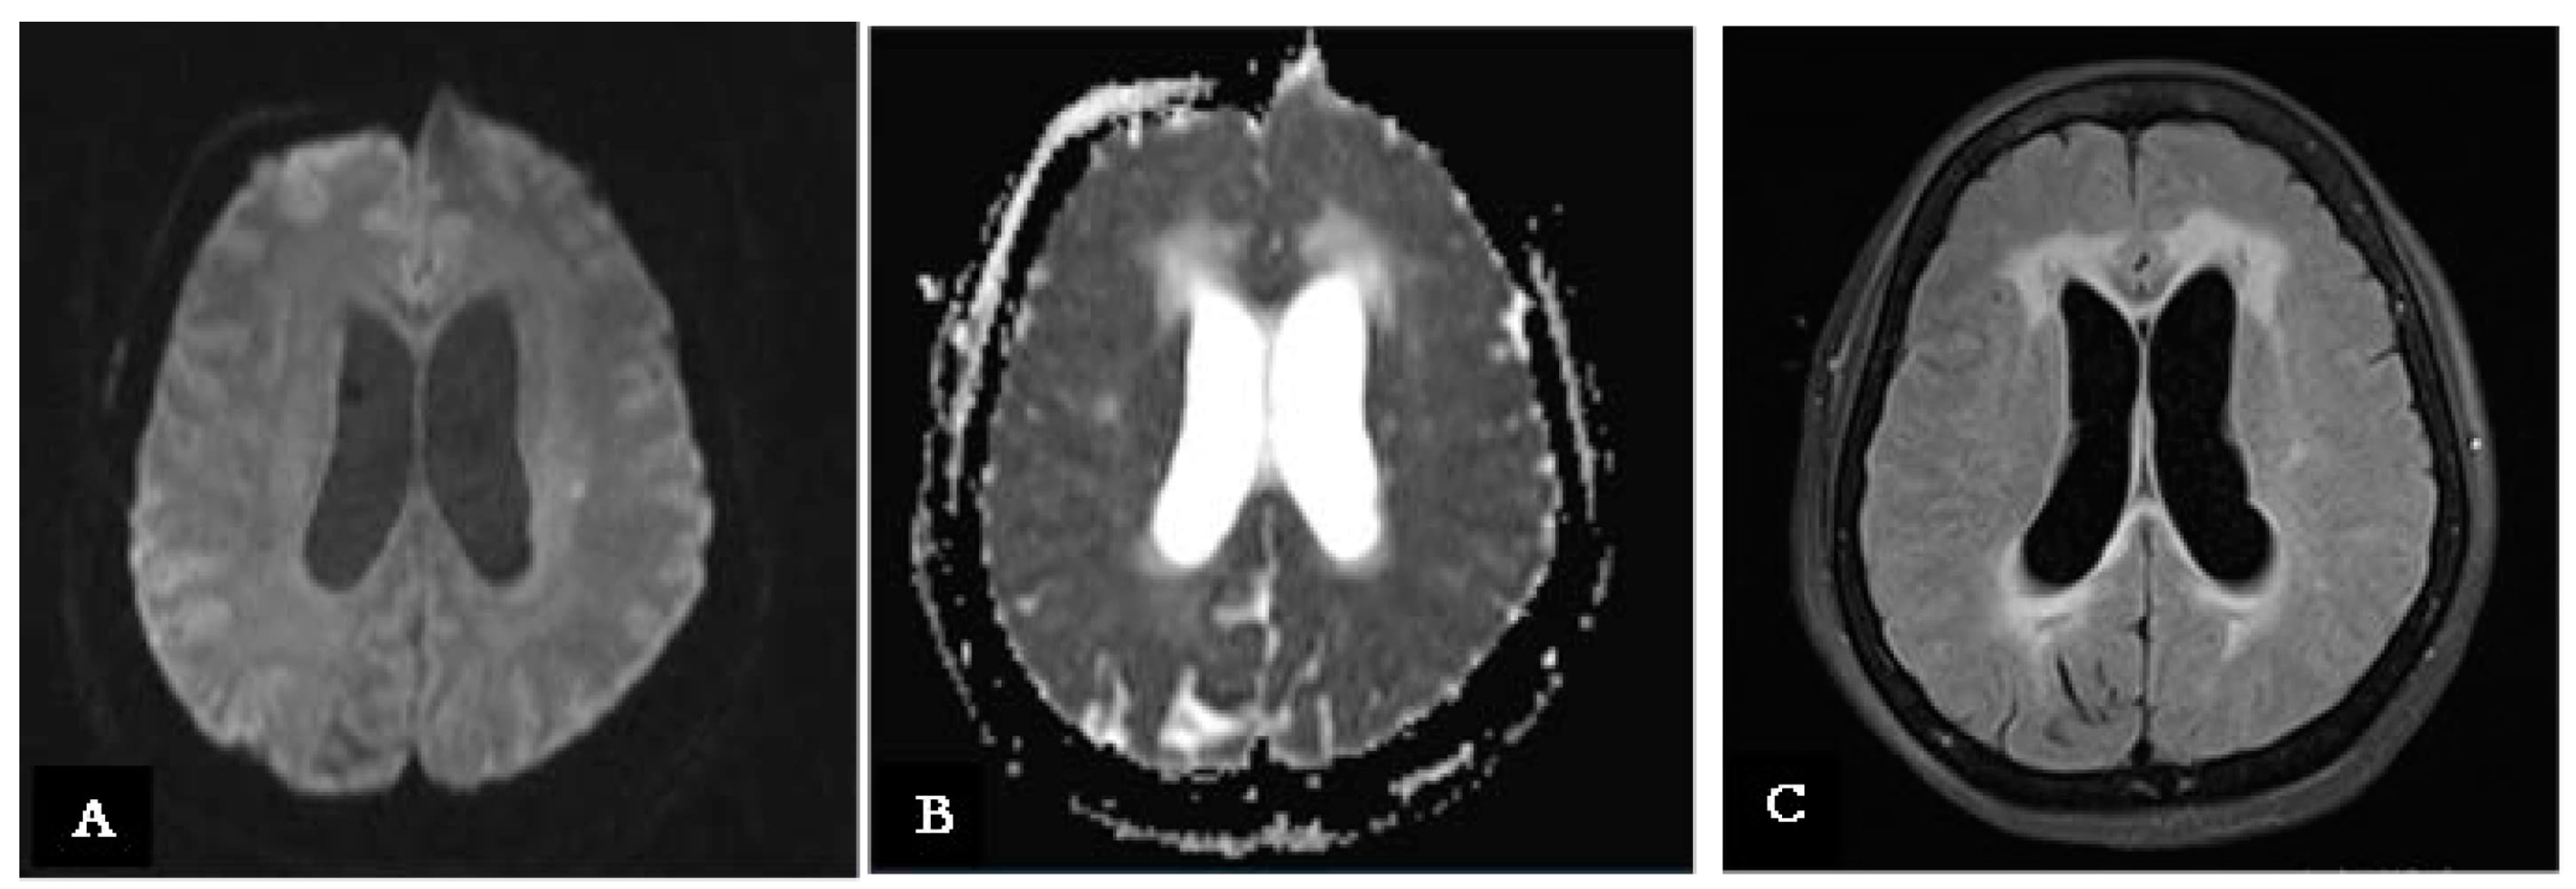

| Day 9 | Improvement in consciousness level. Continued ideomotor slowing, apathy, and abulia. | MRI with contrast: Leptomeningeal enhancement and new ischemic lesion at left corona radiata; hydrocephalus with signs of recent transependymal resorption. |